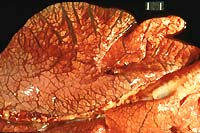

- Gross Pathology: Necropsy findings included blood-stained

perineum, hemorrhage throughout the lumen of the small and large

intestines, and pulmonary edema. Color photo transparencies of

the lungs and intestinal tract are included.

- Case 16-2. Lung. Interlobular septa are markedly expanded

by edema fluid.

- Case 16-2. Spiral colon and jejunum. Colon & small

intestine is segmentally filled with dark red hemorrhage-stained

ingesta. The mesentar appears diffusely edematous.